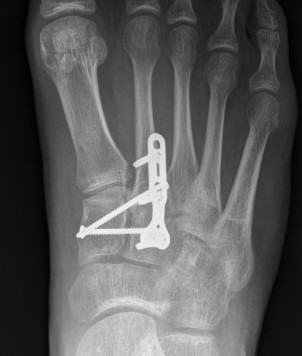

Primary Arthrodesis